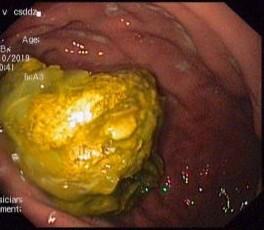

通过会诊评估,李大威医生建议患者通过胃镜进行取石。在进行了完备的术前检查后,消化内科主治医师李大威在护士张令、麻醉医师王鹏程的协助下为患者施行了“无痛胃镜下胃柿石碎石及取石术”。胃镜进入胃腔后,可见一块约4.0cm×4.5cm大小的黄色可移动柿石,并伴有溃疡。此时确诊为:胃柿石、胃溃疡。

李大威医师在尝试使用圈套器将其套住取出时发现,由于柿石过大,无法通过贲门取出。遂用碎石网篮分次分割柿石,化整为零,应用网兜分次取出。历时50分钟后,患者胃内柿石被全部取出。患者不适症状也得到缓解。